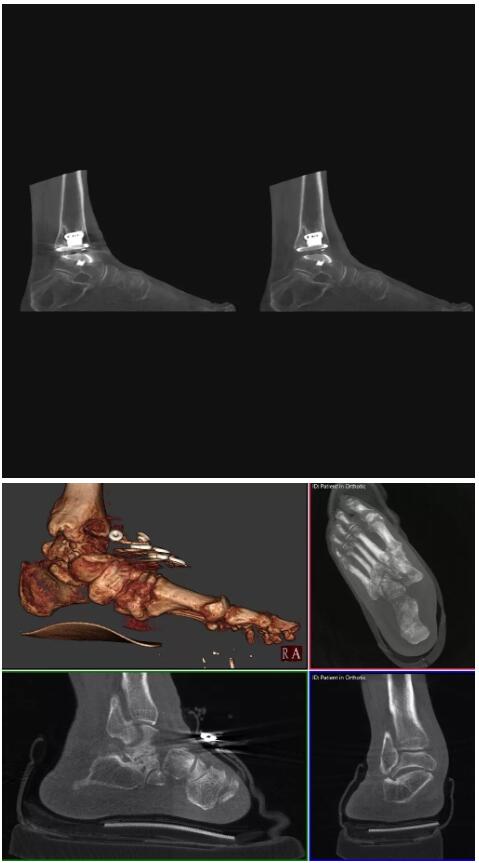

比如上面這款專用于足部和踝部掃查的CT成像系統(tǒng),患者在進行CT掃查時只需要站在上面即可,雙腳站或者單腳站都可以,當然,如果患者不是那么方便站著做完CT掃查,也可坐在上面。

這款CT掃查系統(tǒng)自帶屏蔽裝置,它的體積非常小,僅需要極小的空間即可,并不像常規(guī)CT那樣需要一間單獨的檢查室。此外,這種CT掃查的速度非???,僅需30秒左右可以完成檢查,輻射劑量相對常規(guī)的CT要少許多,尤其適合醫(yī)院的骨科使用。

而患者站著做足部或者踝部做CT檢查還有個好處是,可以檢查患者在負重的情況下,骨關節(jié)的真實情況,而躺著做CT掃查時未必能看出來。負重CT掃查特別是對于受傷的運動員或者舞蹈員來說意義更大,能夠更準確地評估傷情,幫助他們盡早復原。

以下是這些“特立獨行”的CT所拍出來的圖像: